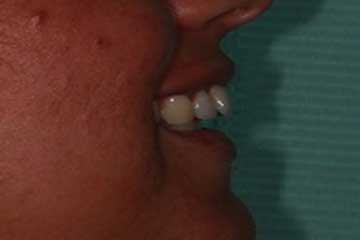

Con protesi fissa superiore e protesi fissa inferiore

sono stati sostituiti da 10 impianti, cioè protesi radicolari endo-ossee che sostengono le protesi fisse superiore ed inferiore.